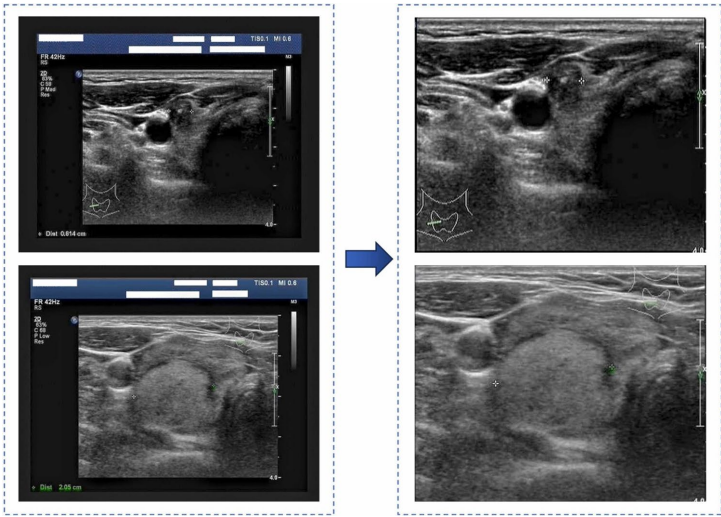

本研究针对甲状腺结节超声图像分类中CNN模型难以捕捉全局上下文信息及医学数据集类别不平衡的问题,提出了一种结合视觉Transformer(ViT)和带梯度惩罚的Wasserstein生成对抗网络(WGAN-GP)的混合模型。该模型利用ViT的自注意力机制提取局部和全局特征,同时通过WGAN-GP生成高质量合成图像以解决数据不平衡问题。在TN5000和UD-TN数据集上的实验表明,该模型准确率分别达到96.8%和97.1%,灵敏度达97.3%-97.5%,显著优于现有方法,为甲状腺结节的自动化诊断提供了可靠工具。